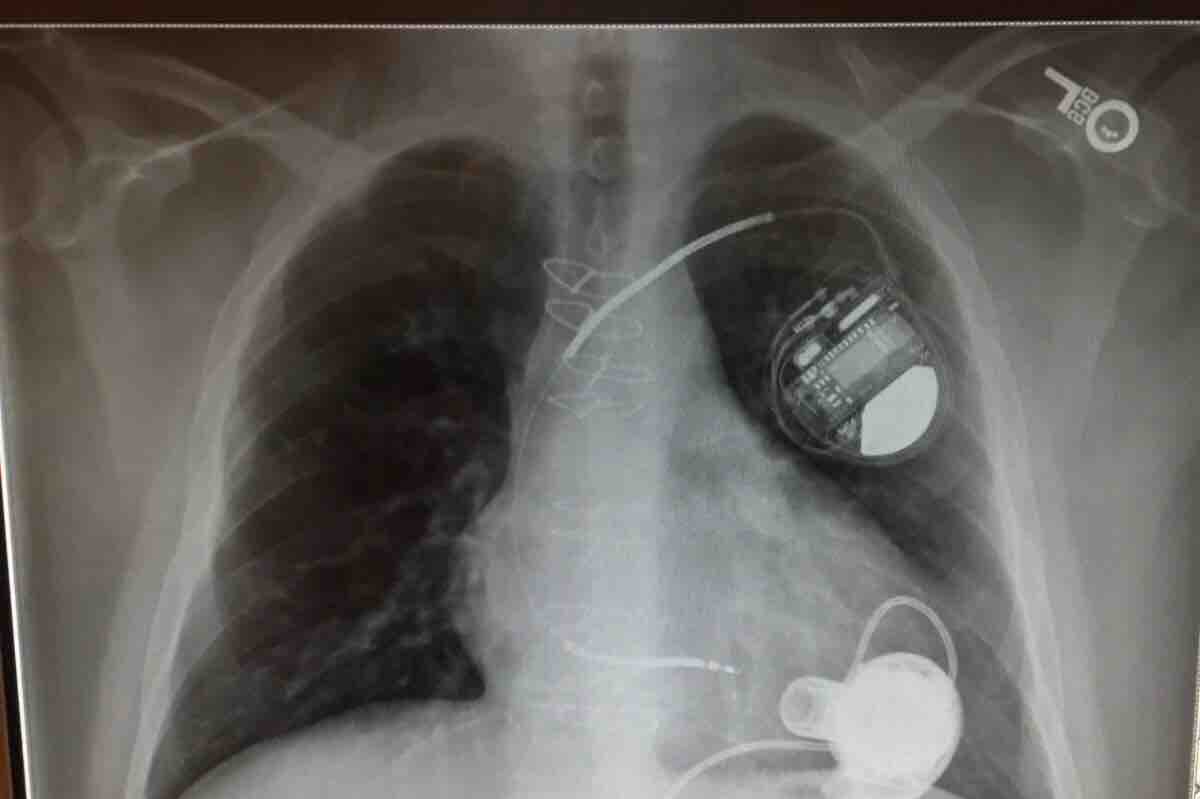

Hi everyone I trying to get some help with medical bills. I have a lot of cost due to getting my life saving heart transplant I can’t work and having to stay away from home for two months as well get my home cleaned from top to bottom because of the medication I am on to suppress my immune system. I live to far they won’t let me go home yet anyway. But having to have duct cleaned carpets and flooring and all furniture cleaned and mattresses covered ect we all know how little ssd is every month I have it spent first night trying to pay bills off. Honestly I got 2.04 in my bank account. And even if you can’t donate please share maybe someone will see anything helps god bless everyone who helps we all have struggles and I always been there to help others . Thank you for reading this